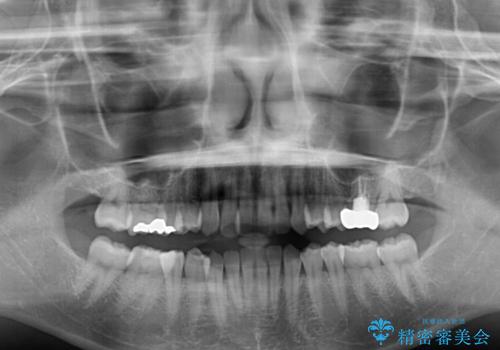

- 前歯のクロスバイトを気にして来院され患者様です。

治療期間が世界的な感染症の流行時期と重なったため、海外と日本での往来が困難となり、治療継続が懸念されました。

それでも、しっかりとマウスピースを装着してくださったので、大きなトラブルもなく治療を終えることができました。